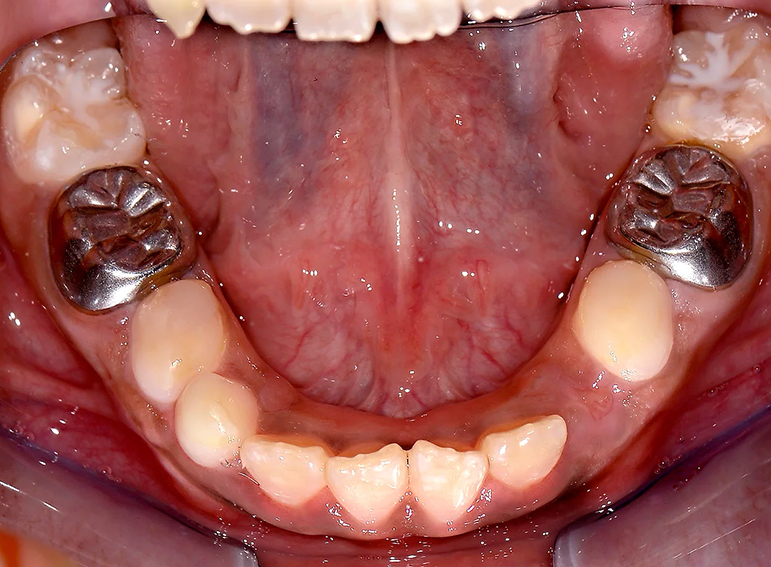

Hypoplastic primary molars: Placement of hall crowns, extraction of URD and ULD, composite restorations of LRD, LLD and C’s and fissure sealants of adult molars.